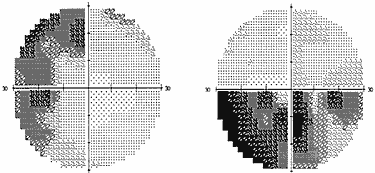

В силу различных причин, в частности, из–за строения диафрагмы турецкого седла, опухоль может распространяться не столько кверху, сколько латерально, в сторону кавернозного синуса – латероселлярный рост. Зрительные нарушения, которые присутствуют при этом росте опухоли, чаще представлены асимметричным хиазмальным синдромом со значительным, вплоть до практической слепоты, понижением остроты зрения на одном глазу. Может также развиться одноименная (односторонняя) гомонимная гемианопсия (рис. 2) в результате воздействия опухоли на зрительный тракт. Дефекты поля зрения появляются в половине поля зрения на стороне, противоположной локализации опухоли. Офтальмологи должны быть внимательны, поскольку дефекты поля зрения при латероселлярном росте опухоли и развитии асимметричного хиазмального синдрома или гомонимной трактусной гемианопсии появляются в носовой половине поля зрения на глазу на стороне преимущественного роста опухоли (рис. 3). Это может спровоцировать ошибочную диагностику глаукомы.

Рис. 2. Полная правосторонняя гомонимная гемианопсия (автоматическая статическая периметрия)

Рис. 3. Начальная левосторонняя гомонимная гемианопсия (автоматическая статическая периметрия)

Помимо зрительных расстройств, характерным для латероселлярного направления роста опухоли является наличие глазодвигательных нарушений в результате либо сдавления медиальной стенки кавернозного синуса опухолью, либо непосредственной инфильтрацией опухолью структур кавернозного синуса.